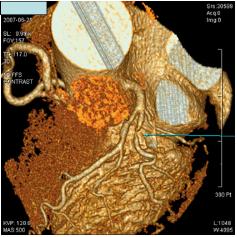

ǽɵ ˻, 24ð Holter ˻, (Ȥ ) ˻, ˻ ̿Ͽ ϰ ȴ. ֱٿ CT˻縦 3 ̰ ִ.

- CT -

Ȯ ˻ Ÿ Ȥ ȸ ̿Ͽ úα ġŰ Ͽ , Ȯϴ ̴.

- -

7) CT, MRI - ǻ Կ 뵿 , ֱٿ ȯ ϰ ֽϴ.